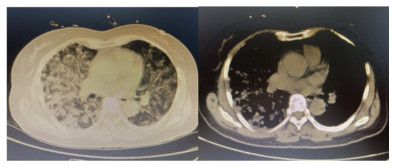

1 资料与方法患者,女,64岁,居住农村,既往有糖耐量异常5年,未正规治疗,4年前诊断为“原发性甲状腺功能亢进”,经治疗已好转。无高风险、中风险地区旅居史,无境外旅居史,无新冠病毒肺炎确诊或疑似患者接触史。2020年7月31日患者无明显诱因下在家中出现发热,体温最高39.4 ℃,伴畏寒、全身乏力,无胸闷、胸痛,无咳嗽、咳痰,无腹痛、腹泻,无黑矇、晕厥,遂在家中自服“退热药”后体温降至正常,但体温仍有反复。8月2日早晨患者再次出现发热,伴畏寒、寒战,遂至本院发热门诊就诊,予查C-反应蛋白156 mg/L,降钙素原0.64 ng/L,考虑感染性发热,遂予“哌拉西林他唑巴坦钠4.5 g每12 h一次”静滴抗感染治疗,后患者突发呼吸费力,伴咳嗽、咯血,为鲜红色血液,量较多,遂于8月2日14:18送达本院急诊抢救室。来时患者呼吸急促,有咳嗽伴咳血性痰,双侧小腿持续性钝痛,查体:血压188/86 mmHg(1 mmHg=0.133 kPa),心率168次/min,呼吸36次/min,血氧饱和度50%,体温38.6 ℃。神志清,精神软,急性面容,双侧结膜略充血,全身皮肤黏膜未见明显充血、淤血,未触及淋巴结肿大。口唇微绀,两肺呼吸音粗,可闻及明显湿性啰音,心律齐,无明显病理性杂音;腹平软,无压痛反跳痛,四肢肌力Ⅴ级,两侧病理征未引出。予心电监护、特级护理、面罩吸氧、建立静脉通道,送检血常规、生化、血气、心肌酶、凝血酶原时间系列、痰培养等常规检查,同时予送检血标本行高通量测序,完善胸部CT检查(图 1)。辅助检查结果如下:8月2日胸腹部CT示两肺感染,腹部未见明显异常。血常规:白细胞计数7.9×109/L,中性粒细胞百分比89%,血红蛋白121 g/L,血小板计数104×109/L,C-反应蛋白156.82 mg/L。血生化:丙氨酸氨基转移酶51 U/L,天门冬氨酸氨基转移酶63 U/L,白蛋白34.5 g/L,总胆红素17.4 mmol/L,肌酐74 mol/L。心肌酶谱:心肌肌钙蛋白I 0.014 ng/mL,肌红蛋白322 ng/mL,肌酸激酶同工酶3.2 ng/mL。血气分析:pH 7.435,二氧化碳分压29 mmHg,氧分压53.5 mmHg,K+ 2.6 mmol/L,Na+ 132 mmol/L,血乳酸3.1 mmol/L。新型冠状病毒抗体、核酸阴性。接诊医师初步诊断为“咯血待查:疑似肺部感染,呼吸衰竭”,治疗上予亚胺培南0.5 g静滴经验性抗感染、甲泼尼龙80 mg静滴抗炎,同时予化痰、平喘等对症、支持。17:00患者出现呼吸费力加重,10 L/min面罩吸氧下血氧饱和度仍为70%,故予紧急气管插管、机械通气,随后转入ICU,联系感染科医师会诊,结合患者病史及CT影像学表现的广泛、片状密度增高影特点,考虑钩端螺旋体病可能性大,不排除“赫氏反应”,故继续予亚胺培南0.5 g静滴每6 h一次抗感染、甲泼尼龙80 mg静滴每12 h一次抗炎、白蛋白营养支持等治疗。8月3日更改甲泼尼龙80 mg静滴每天一次。8月4日高通基因测序回报:检测出问号钩端螺旋体DNA,符合入院时推断,明确病原体后予修正诊断为肺出血型钩体病伴赫氏反应。8月5日停亚胺培南,改青霉素160万单位静滴每8 h一次。8月8日患者病情稳定,拔除气管导管,予甲泼尼龙减量为40 mg静滴1次/d,8月9日复查胸部CT提示两肺斑片状、片状密度增高影较前有所吸收(图 2),停用甲泼尼龙。8月10日转入呼吸科。8月17日复查胸部CT提示两肺斑片状、片状、条索状密度增高影,较前明显吸收(图 3)。8月20日患者好转出院。9月18日随访,复查CT提示两肺散在条索状密度增高影,基本恢复正常(图 4)。

| 图 1 8月2日入院时胸部CT呈弥漫性密度增高影 |